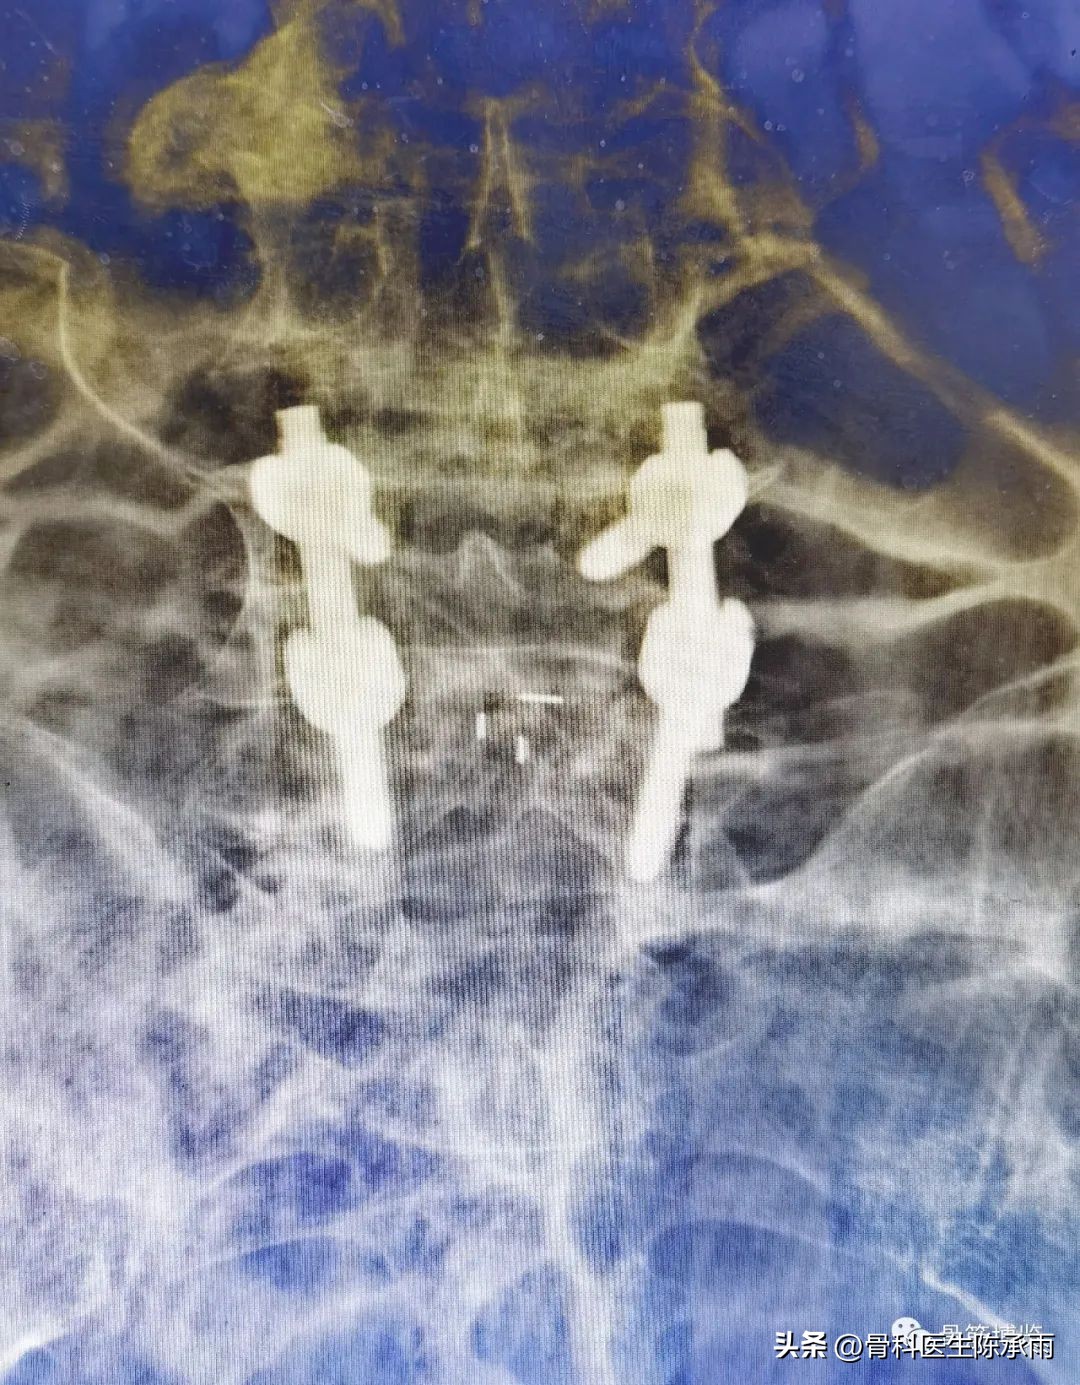

术中C臂

术中固定情况:后路全椎板减压,钉棒固定,两个间隙的椎间融合

术后影像